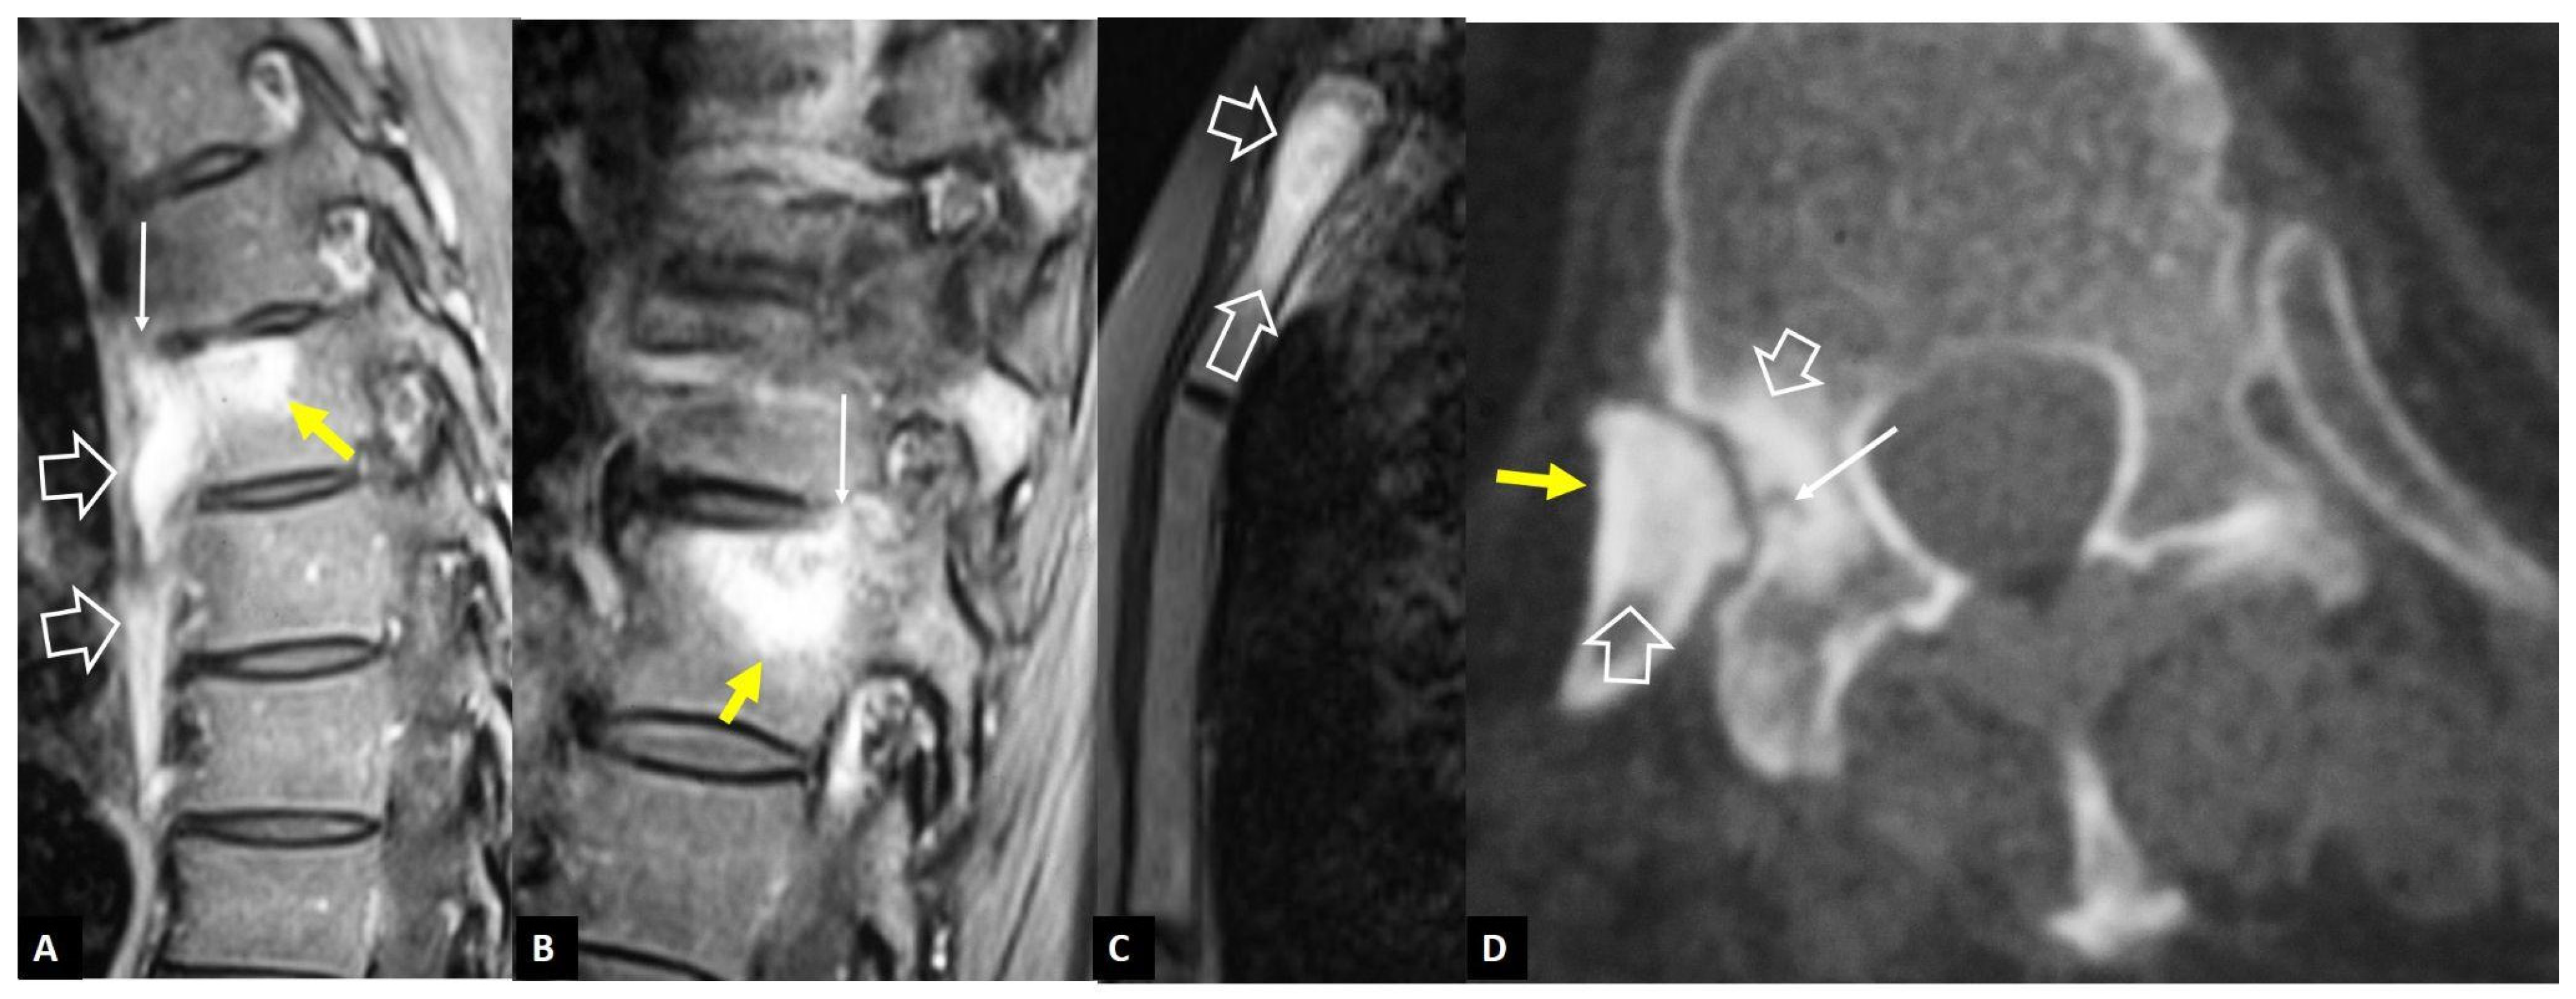

2.1.3. SAPHO Syndrome

2.1.4. Destructive Spondyloarthropathy

2.2. Non-Infectious Sacroiliitis